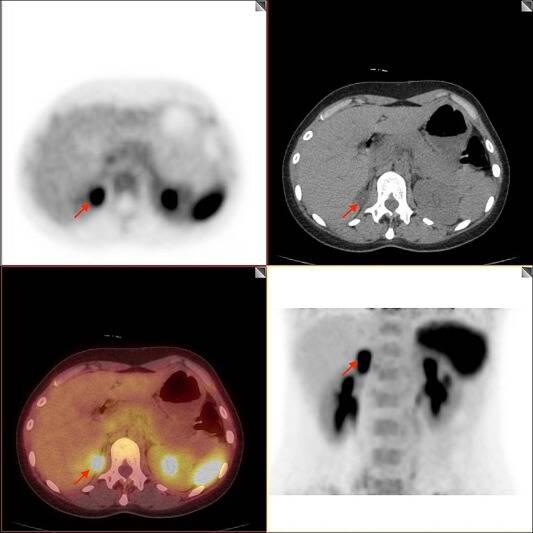

Recently, a new imaging technique for this condition has been developed at University College London, and it has proven to be more accurate and less invasive - PET-CT scans can detect and show the hyperactivity of one or both of the adrenal glands in Primary Aldosteronism (something which is invisible in other scans) on a detailed 3D image. This reduces the time taken for a diagnosis to be made, reduces hypertension-driven risks to a patient's health and the accumulation of the damage to the body from this condition.

See above: PET-CT Scans showing Primary Aldosteronism.

The two scans described above can be combined into a PET-CT scanner, where the radioactive tracer detecting high cell activity and the detailed 3D X-Ray images can be combined to show specialists the structure and performance of the body. In the case of Primary Aldosteronism, this new diagnostic technique is not only far less invasive, but due to its high accuracy and speed, shows promise for solving the problem of under-diagnosis and ensuring patients can receive the correct treatment sooner.